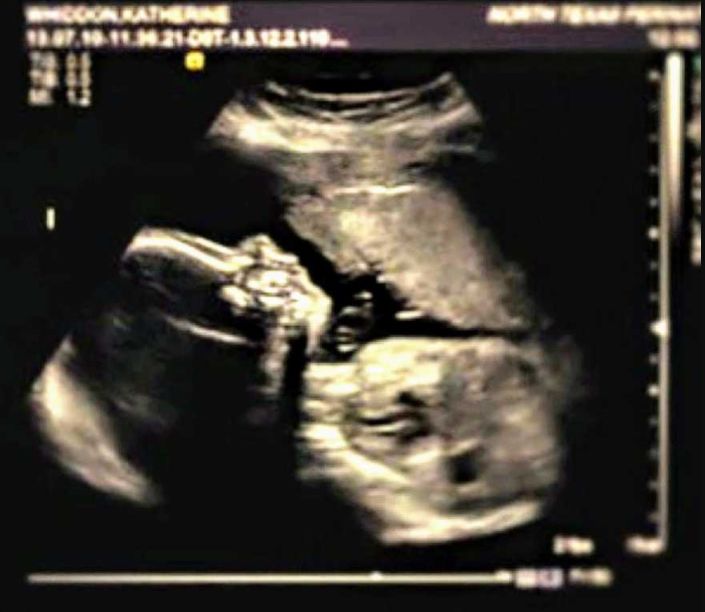

5月,怀孕18周时,她照例去医院产检。“是个男孩儿!”医生笑着告诉她,凯特也幸福地笑了。

可下一秒,医生面色凝重,些许迟疑地说:“恐怕事情有些糟糕......我看不到他的胳膊和腿......”

天降噩耗,凯特的宝宝天生残疾,很有可能活不长久。

2013年10月,孩子出生了,体重只有4.4斤,取名为卡姆登。

出生检查显示:卡姆登一切体征正常,无伴随症。这算是天大的好消息。